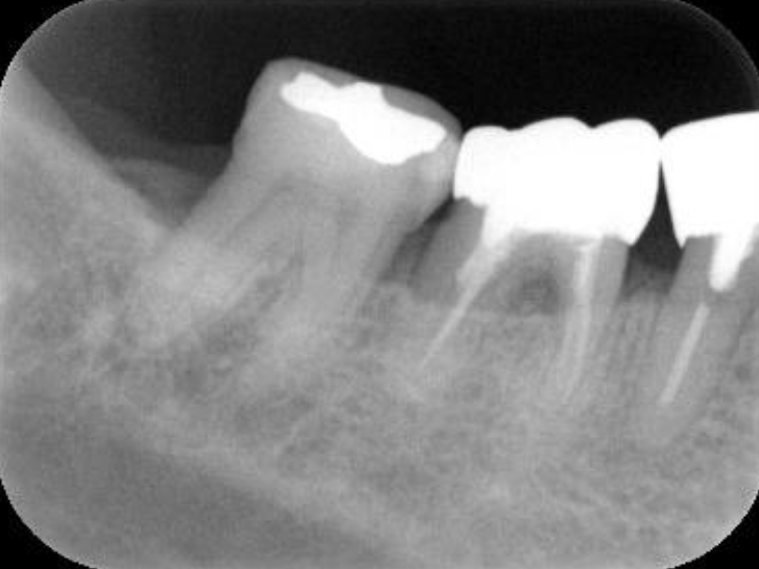

初診時(レントゲン)

浜松市中区の症例紹介 歯周外科

歯周基本治療・根管治療後(レントゲン)

歯周外科処置後

(レントゲン)

初診時年齢:

治療:歯周病治療・う蝕治療

治療法:歯周基本治療、歯周外科治療、感染根管治療

治療期間:1年3ヶ月

費用:保険診療

リスク・副作用:歯周外科処置後に出血、腫れ、あざが出ることがありますが時間とともに治ります。術後3週間程度噛んだときの痛みや歯が浮いた感じがすることがあります。

感染根管処置中に腫れ、痛みが出ることがありますが時間とともに治ります。